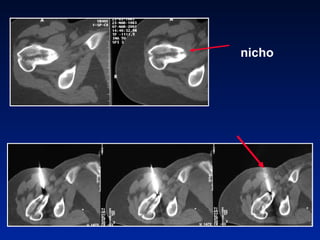

Vía direta    Vía retrógada Ressecção ossea percutanea

nicho